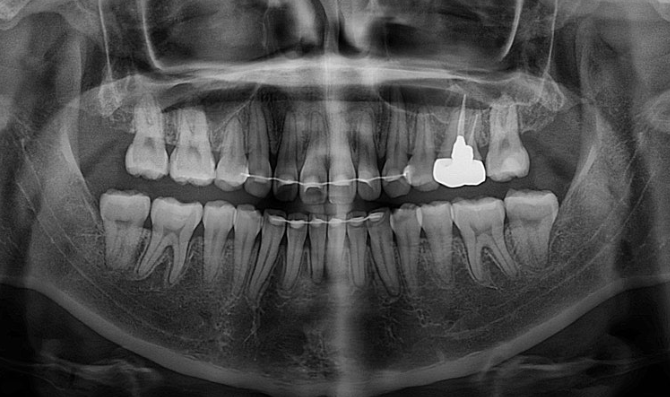

There is no sign of root resorption, and root parallelism is also good.

The total treatment period was 1 year and 8 months, which is under 2 years.